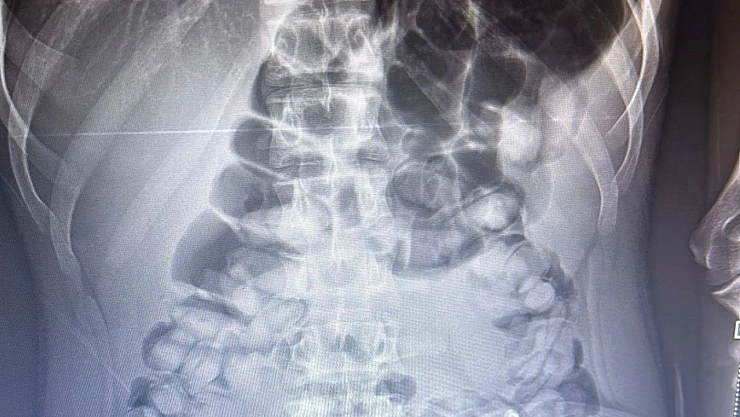

Erzurum Emniyet Müdürlüğü Narkotik Suçlarla Mücadele Şube Müdürlüğü ekipleri tarafından yapılan operasyonda bir şahsın karnından 1 kg 134 gram Afyon Sakızı maddesi çıkarıldı.

Emniyet Müdürlüğü tarafından konu ile ilgili yapılan açıklamada şöyle denildi,” Uyuşturucu madde ticareti ve sevkiyatına yönelik yapılan çalışmalar neticesinde 13.11.2023 tarihinde tespit edilen yolcu otobüsünde durumunlarından şüphelenilenerek uyuşturucu madde yutmuş olabileceği değerlendirilen ve İlimiz Şehir Hastanesinde iç beden muayenesi yaptırılan S.A. (2006 doğumlu) isimli şahıstan toplam 1 kg 134 gram Afyon Sakızı maddesi ele geçirilmiş, konuyla ilgili adli mercilere sevk edilen şahıs tutuklanarak cezaevine teslim edilmiştir. Uyuşturucu veya uyarıcı madde satışı, kullanımı ve nakli ile ilgili mücadelemiz kararlılıkla sürdürülecektir.”